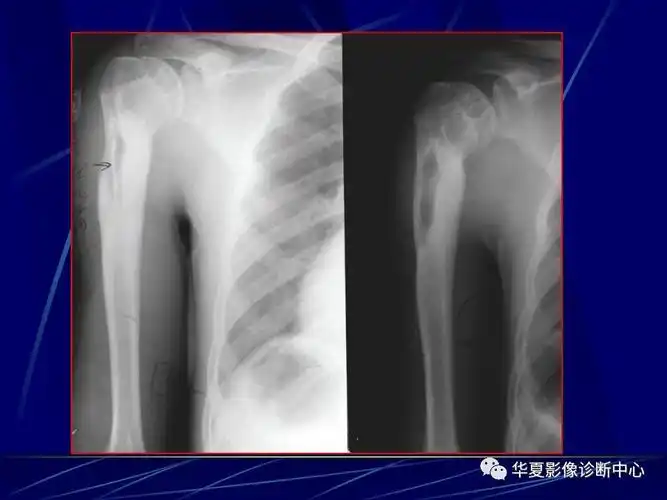

骨化脓性骨髓炎的影像学诊断